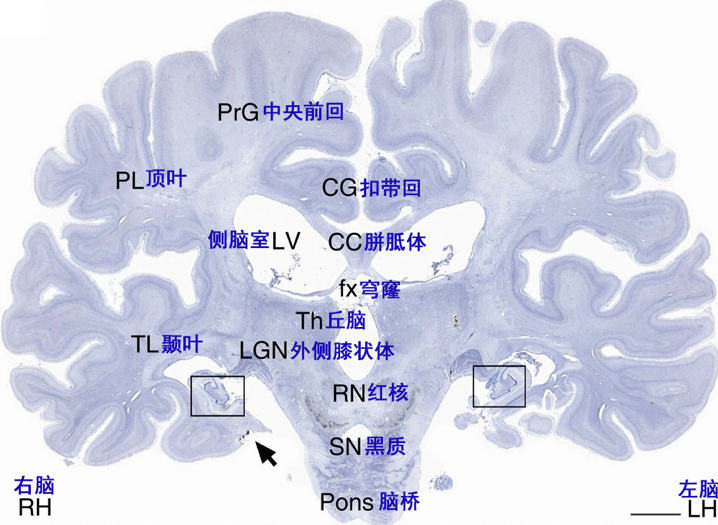

本文图片

图5 H.M.去世后大脑组织尼氏染色切片 , 方框及箭头所指为海马